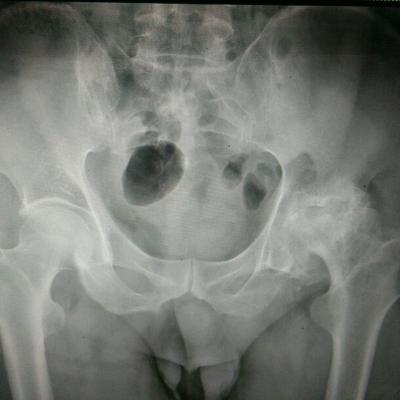

患者女,40岁,医院职工家属。B超体检时发现肝肾间多发囊性占位性病变。行腹部平扫示:右肾上腺区囊性占位,有分割和钙化点,右肾受压下移。诊断意见:右肾上腺囊腺瘤可能性大,建议进一步检查明确。后到市级医院检查并切除手术,病理切片考虑肾上腺囊肿。今腰部不适复查CT片。